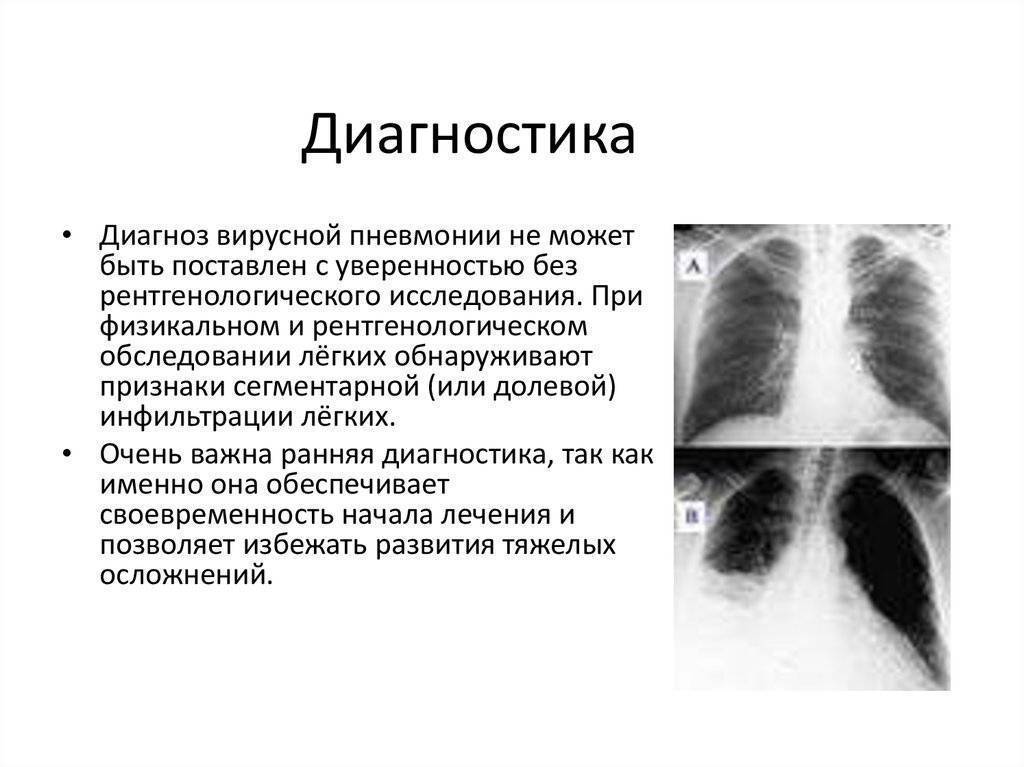

Нужны ли особые методы диагностики при ведении пациентов с вирусной пневмонией?

Сергей Авдеев: Да, безусловно. Сегодня большой акцент делается на компьютерной томографии легких. Этот метод относится к имидж-диагностике, как и рентгенография. Но компьютерная томография — более точная и специфичная методика выявления изменений в ткани легких по сравнению с обычной рентгенографией. Большинству пациентов с COVID-19 как раз и требуется такая методика. Компьютерную томографию я бы поставил сегодня на первое место среди всех имеющихся методов для подтверждения диагноза. По своей чувствительности она даже превосходит лабораторную диагностику для подтверждения вирусной инфекции. Чувствительность компьютерной томографии превышает 90%.

В то же время у 2-30% больных COVID-19 возможны отрицательные результаты лабораторной диагностики. Это связано не с качеством реагентов или тестов. Просто существуют определенные условия, которые накладывают отпечаток на результаты. Это время возникновения инфекции, место забора биологического материала, качество забора и так далее. И получается, что с помощью компьютерной томографии сам случай коронавирусной инфекции иногда виден раньше, чем при использовании лабораторных тестов.

Отличается ли снимок компьютерной томографии у пациента с коронавирусной пневмонией и обычной пневмонией?

Сергей Авдеев: Да, отличия существенные. При COVID-19 практически всегда пневмония двусторонняя, расположена по периферии легких (под плевральной оболочкой). На начальных этапах она имеет вид, как говорят рентгенологи, «матового стекла». При прогрессировании изменения становятся более плотными и распространенными. А затем происходит фаза обратного развития — уменьшение размера и плотности легочных инфильтратов.